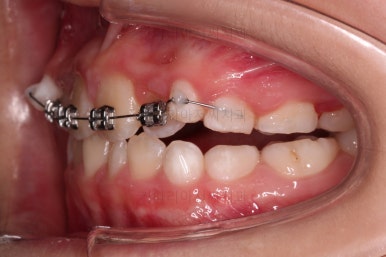

마찬가지로 초진 시 입안의 모습이에요.

아래 앞니가 윗니보다 앞에 있는 "반대교합" 즉, 거꾸로 물려있는 상황이었고요.

어금니 쪽을 보시면(왼쪽 위 사진) 윗니 어금니도 아래 어금니보다 안쪽으로 들어와 있는 "어금니 반대교합"도 있는 상황이었어요.

즉, 윗니가 있는 위턱뼈가 3차원적으로 작은 상황이었던거죠.

이렇게 아랫니들이 윗니보다 앞으로 나와있는 형태의 부정교합을 "앵글씨 3급" 부정교합이라고 합니다.